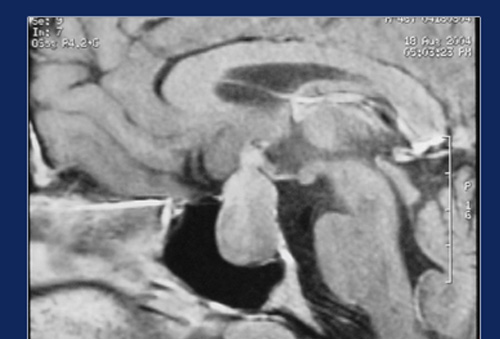

The pituitary gland is a tiny body about the size of a peanut situated at the center of the skull with its stalk attached to the base of the brain. It produces a number of hormones, which control other endocrine glands. Sometimes a tumor of this gland can result in hormonal imbalance with growth and other metabolic derangements. The neurosurgical approach to this gland is fraught with difficulties owing to its location and vision shadow areas, and also injury to cranial nerves and other parts of the brain.

This gland can be very easily approached through the nose under Endoscopic control, since it is just a thin plate of bone away from the sphenoid sinus. Sphenoid sinus is routinely opened during Endoscopic nasal surgery to open the pituitary fosse through this sinus. Complete removal of tumor is possible since there are no vision shadow areas in this approach.